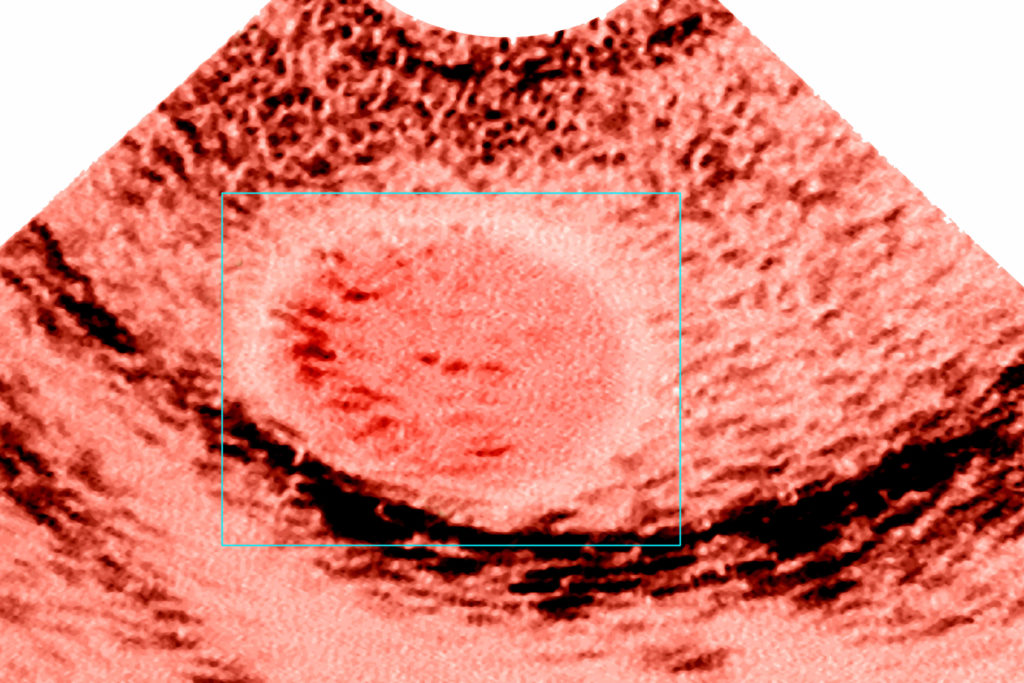

Maszkot viselünk, az orvos és én is, mégis látom az arcán a sokkot. Türelmes, igazán jó fej ember, aki az első betegségem idején is őszinte, határozott válaszokat ad az összes – sokszor buta – kérdésemre. Most is ilyen. Elmondja, hogy amit lát, nagyon apró, szerinte 9×6 milliméteres góc, de bevon egy professzort, hogy legyen másodlagos szakvélemény is. „Kitapintani nem tudom, ez mindig gyanús, talán rezekálható” – mondja – de én már tudom, hogy ettől meg kell szabadulni. Ettől is.

Hererák az ultrahang képén (Fotó: BSIP/UIG Via Getty Images)